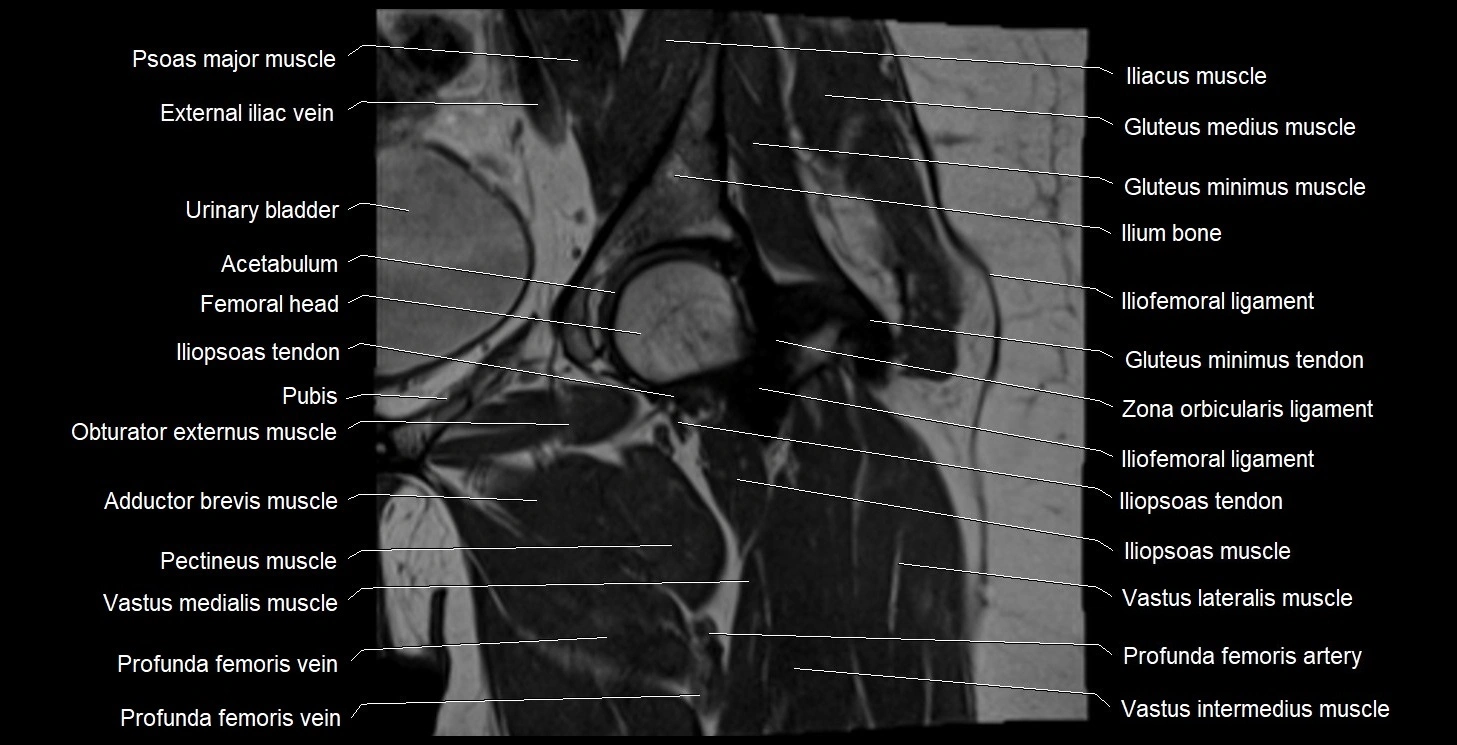

- Acetabulum

- External iliac vein

- Iliopsoas muscle

- Iliopsoas tendon

- Iliofemoral ligament

- Ilium bone

- Urinary bladder

- Vastus intermedius muscle

- Vastus lateralis muscle

- Vastus medialis muscle

- Zona orbicularis ligament

- Deep femoral artery (profunda femoris)

- Deep femoral vein (profunda femoris vein)

- Obturator externus muscle

- Pectineus muscle

- Psoas major muscle

- Adductor brevis muscle